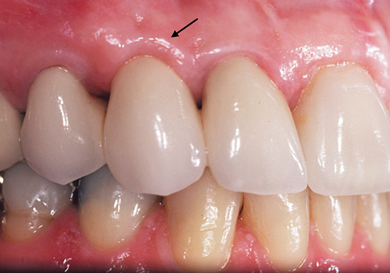

(10.) Close-up view of the existing edentulous tooth No. 10 site prior to the creation of the ovate pontic site.

Figure 10

A patient presented with two defective 3-unit fixed partial dentures spanning teeth Nos. 6 through 8 and teeth Nos. 9 through 11 (Figure 7). The defective fixed partial dentures were removed (Figure 8), an impression was made, and traditional provisional fixed partial dentures without ovate pontics were placed. After the impression was sent to the laboratory, the lab technician prepared ovate pontic sites on the stone cast (Figure 9) and fabricated the new definitive bridges. On the day of insertion, the provisional fixed partial dentures were removed (Figure 10), ovate pontic sites were prepared using a teardrop-shaped diamond bur (Figure 11), and the sites were sounded to confirm that there was at least 2 mm from the base of the pontic site to the alveolar bone (Figure 12). The fixed partial dentures were cemented, and the postoperative healing was uneventful (Figure 13).

It is essential that an ovate pontic be convex in all dimensions. However, with the traditional "egg in the nest" shape, the gingival marginal tissue over the facial aspect of the pontic is commonly rolled rather than knife edged, which can result in a shadow (Figure 1) and give away that it is a pontic rather than a natural tooth. Therefore, the critical issue isn't the shape of the intaglio surface of the pontic but rather the emergence profile of the pontic on its facial surface. Where the facial aspect of an ovate pontic emerges from the soft tissue, it should have the same contour as a natural tooth. Therefore, it should not be rounded. The facial aspect of an ovate pontic should have a flat surface that goes approximately 1.0 mm under the gingival crest before it starts to become rounded (Figure 2). The shape of the rounded surface of the pontic is determined by the thickness of the ridge in the created site. It will be more round for a thick ridge and more pointed for a thin ridge.